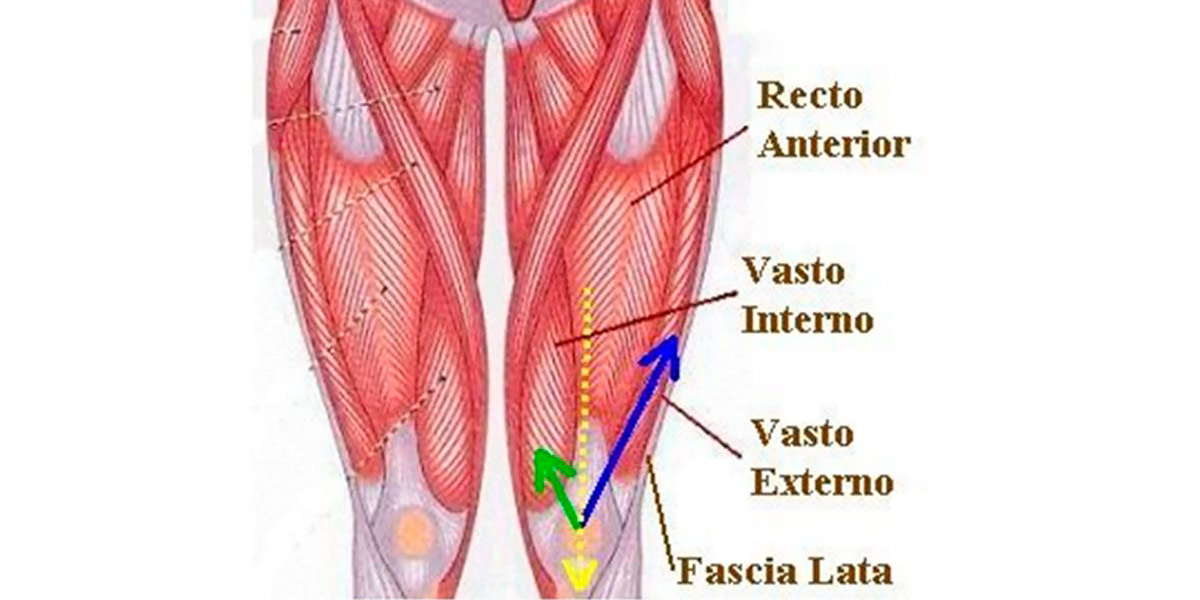

Músculos da coxa

Um grande enfraquecimento dos quadríceps (Crossley et al., 2016) além de uma grande predominância dos isquiosurais (White et al., 2009), são um fator de risco no desenvolvimento do síndrome do joelho de corredor.

No entanto, por vezes o diagnóstico não é assim tão simples, uma vez que os desequilíbrios na produção de força nos diferentes músculos que constituem o quadríceps também podem alterar a rótula e causar o efeito de desvio patelar.

Figura VII. Representação gráfica dos diferentes graus do ângulo Q e as suas consequências sobre o deslocamento do joelho.

Denomina-se por ângulo Q o ângulo que é formado pela linha da espinha ilíaca superior com a parte centrar da rótula, e a linha da parte central da rótula até à tuberosidade da tíbia; e determina o vetor de força do quadríceps (vemos de forma mais clara na imagem seguinte).

Figura VIII. Representação gráfica do ângulo Q. Fq é o vetor de força do quadríceps, Fp é o vetor de força patelar, e Rl é o resultado líquido das forças.

Geralmente, as pessoas com síndrome do joelho de corredor possuem um externo forte e amplo do quadríceps (a parte de fora da parte anterior da coxa) e um interno fraco e amplo (o contrário).

Figura IX. Miologia da coxa.